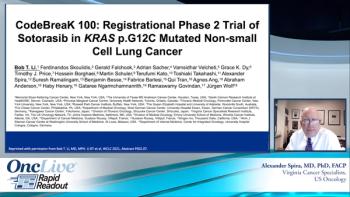

Alexander Spira, MD, PhD, FACP, presents slides from the International Association for the Study of Lung Cancer 2020 World Conference on Lung Cancer (WCLC) from CodeBreak 100, the phase 2 trial of sotorasib in KRASG12C-mutated non–small cell lung cancer.

Bob T. Li, MD, PhD, MPH, discusses the efficacy of sotorasib in patients with KRAS G12C–mutated advanced non-small cell lung cancer, as demonstrated in phase 2 cohort results of the phase 2 CodeBreaK 100 trial.